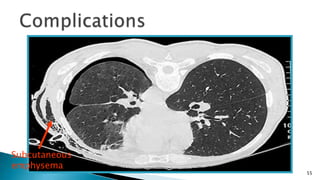

Mediastinal and subcutaneous emphysema

◦ Alveoli rupture, the air enter into pulmonary

interstitial, and then goes into mediastinal and

subcutaneous tissues.

◦ After aspiration or intercostal chest tube insertion,

the air enters the subcutaneous by the needle hole

or incision – surgical emphysema

◦ Physical exam – crepitus is present.

55

Subcutaneous

emphysema